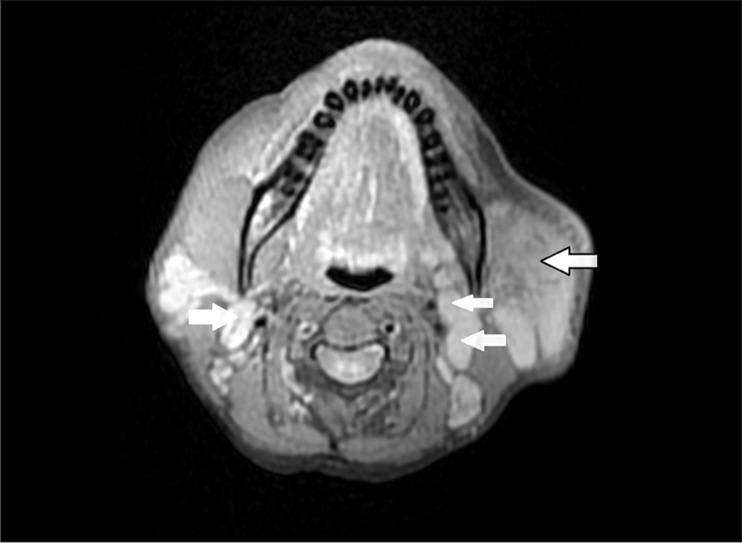

A middle-aged female patient presenting with a history of multiple chronic neck swellings was thoroughly evaluated by ultrasound (US), computed tomography (CT), and magnetic resonance imaging (MRI). The imaging findings included gross enlargement of the left parotid gland, a focal lesion in the right parotid gland, and cervical lymphadenopathy. These features correlated with histopathological findings, and the diagnosis of Kimura disease was made.

一名有多处慢性颈部肿胀病史的中年女性患者接受了超声(US)、计算机断层扫描(CT)和磁共振成像(MRI)的全面评估。影像学表现包括左侧腮腺明显肿大、右侧腮腺局灶性病变以及颈部淋巴结病。这些特征与组织病理学结果相关,从而做出了木村病的诊断。